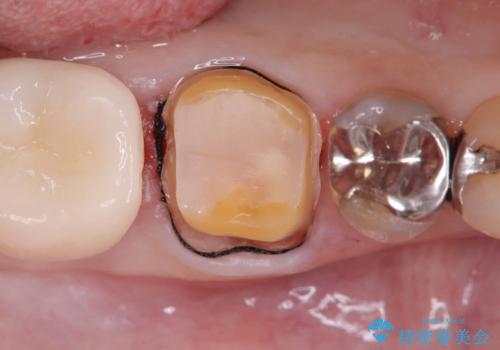

銀歯の下の虫歯|オールセラミッククラウン

- メンテナンスで虫歯が見つかり、治療を行いました。

まず既存の銀歯を除去し、虫歯を取り除いた後、オールセラミッククラウンで修復しました。

銀歯の下は、目に見えないうちに虫歯が進行していることがよくあります。

特に古くなった銀歯や、咬み合わせの圧力で微細な隙間ができた場合にリスクが高くなります。